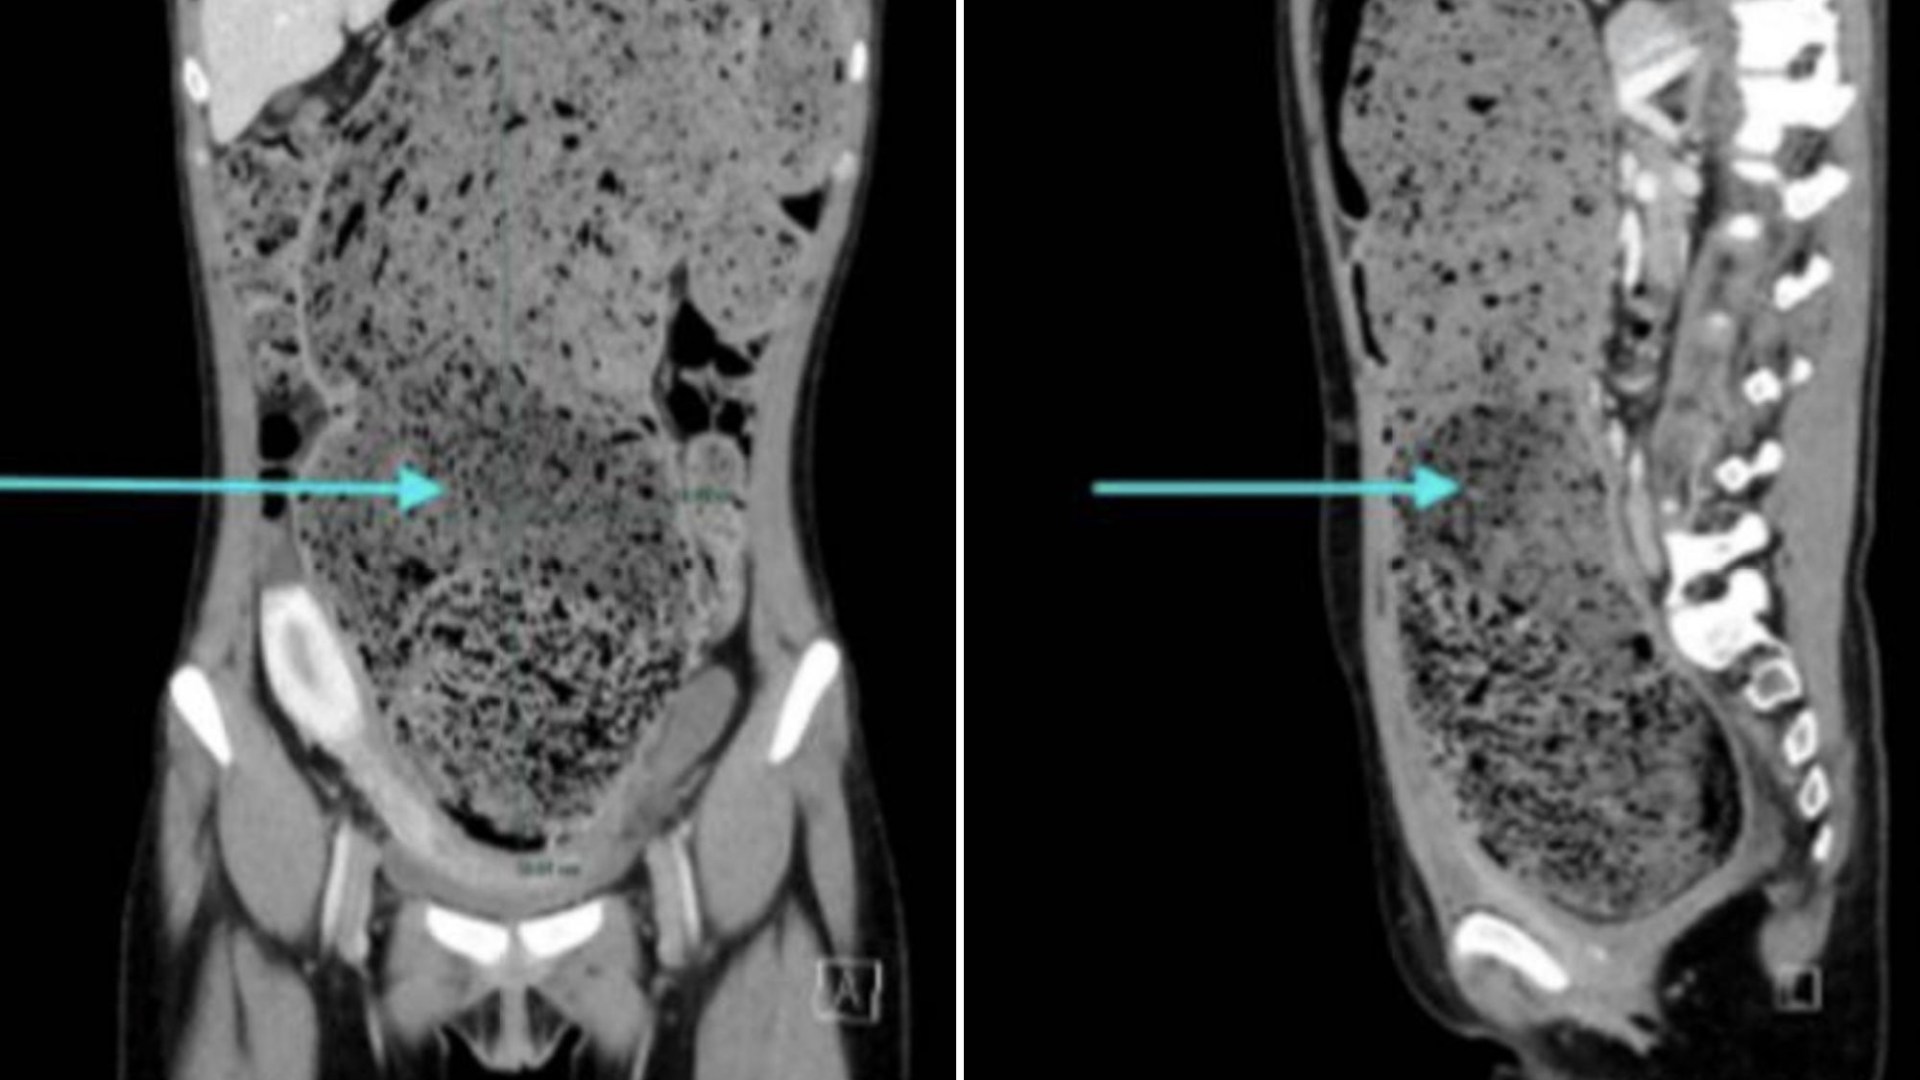

25 years old experiences chronic constipation, with a history of constipation reducing during junior/high school. HerCondition includes bloating, weight loss, and pain. After four months of constant suffering, doctors examined her using explorers and found a blockage in her abdomen, relaying indents when she pressed on her stomach. A CT scan revealed her gastrointestinal tract with editosomes (blockages likely forming stools), and she opted for manual disimpaction to break down stools.

Doctors diagnosed her with faecal impaction: a blockage of her last large intestine, often linked to constipation. She had a 15cm diameter redundant sigmoid colon, an unusually long colon, potentially causing more frequent constipation. Single-needle disimpaction was ruled out due to difficulty maneuvering the colon, leading to repeated 10-15 minute procedures.